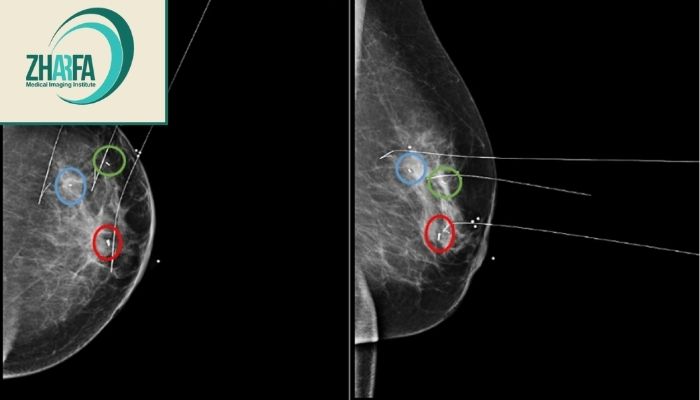

ماموگرافی ضایعه کوچیکی نشون داد که با دست حس نمیشد. و این روش باعث شد جراح راحت پیداش کنه.